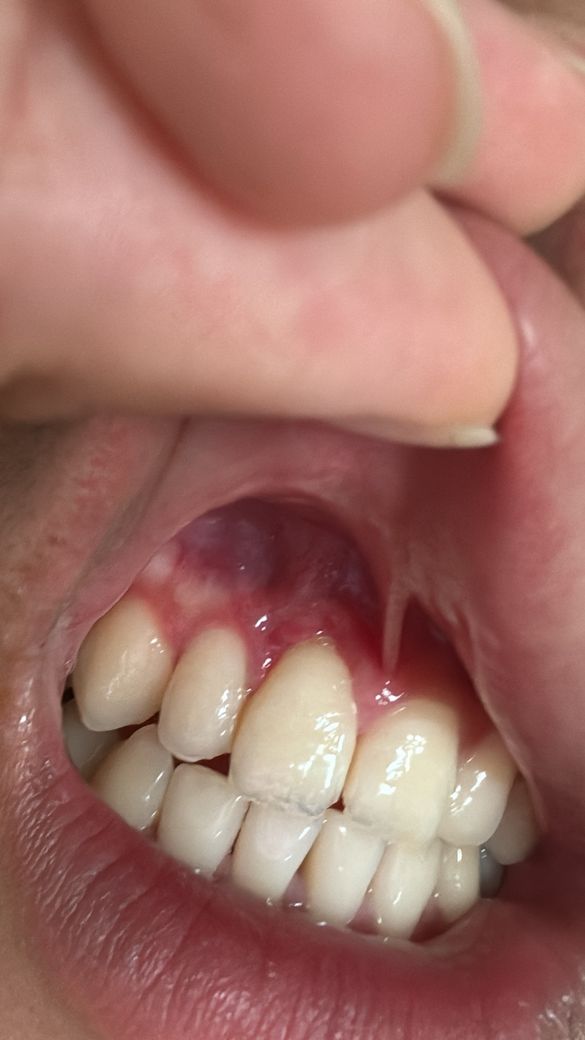

잇몸 절개 수술하고 2주정도 됐는데 잘 회복되고 있나요?

잇몸 절개 수술하고 2주 정도 지났는데 잘 회복되고 있나요? 그리고 이제 담배 펴도 아무문제 없을까요? 더이상 못참을거같아요..

• 1번 째 사진

사진상으로 잇몸이 잘 아물고 있는거 같습니다. 2주 정도 지낫다면 흡연을 하셔도 문제가 되진 않을것같습니다.

사진으로 봤을 때 잇몸은 잘 아물고 있는 것으로 보입니다. 흡연은 잇몸이 치유되는 것을 늦출 수 있기 때문에 피지 않는 것이 좋습니다.

사진상으로는 특별히 문제가 보이지는 않습니다. 흡연은 2주정도 지나셨다면 해도 됩니다.

절개 부위가 어느정도 아물긴 했으나 전부 다 아물진 않았습니다. 흡연은 가급적 삼가는 것이 좋겠습니다